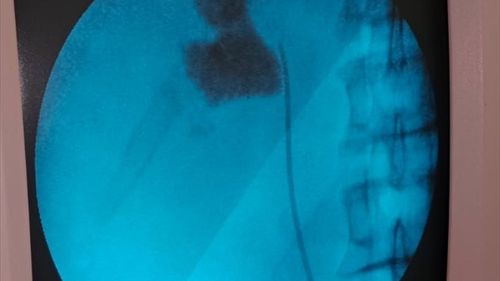

Kırşehir'de, Eğitim ve Araştırma Hastanesi'nde bir hastanın böbreğindeki 6 santimetrelik taş, kapalı ameliyat yöntemiyle alındı. Hastaneye başvuran İlhami Çakır'ın yapılan kontrollerinde, sol böbreğinde 6 cm boyutunda bir taş tespit edildi. Üroloji Kliniği'nden Uzm. Dr. Talip Göktaş ve ekibi, kapalı böbrek…